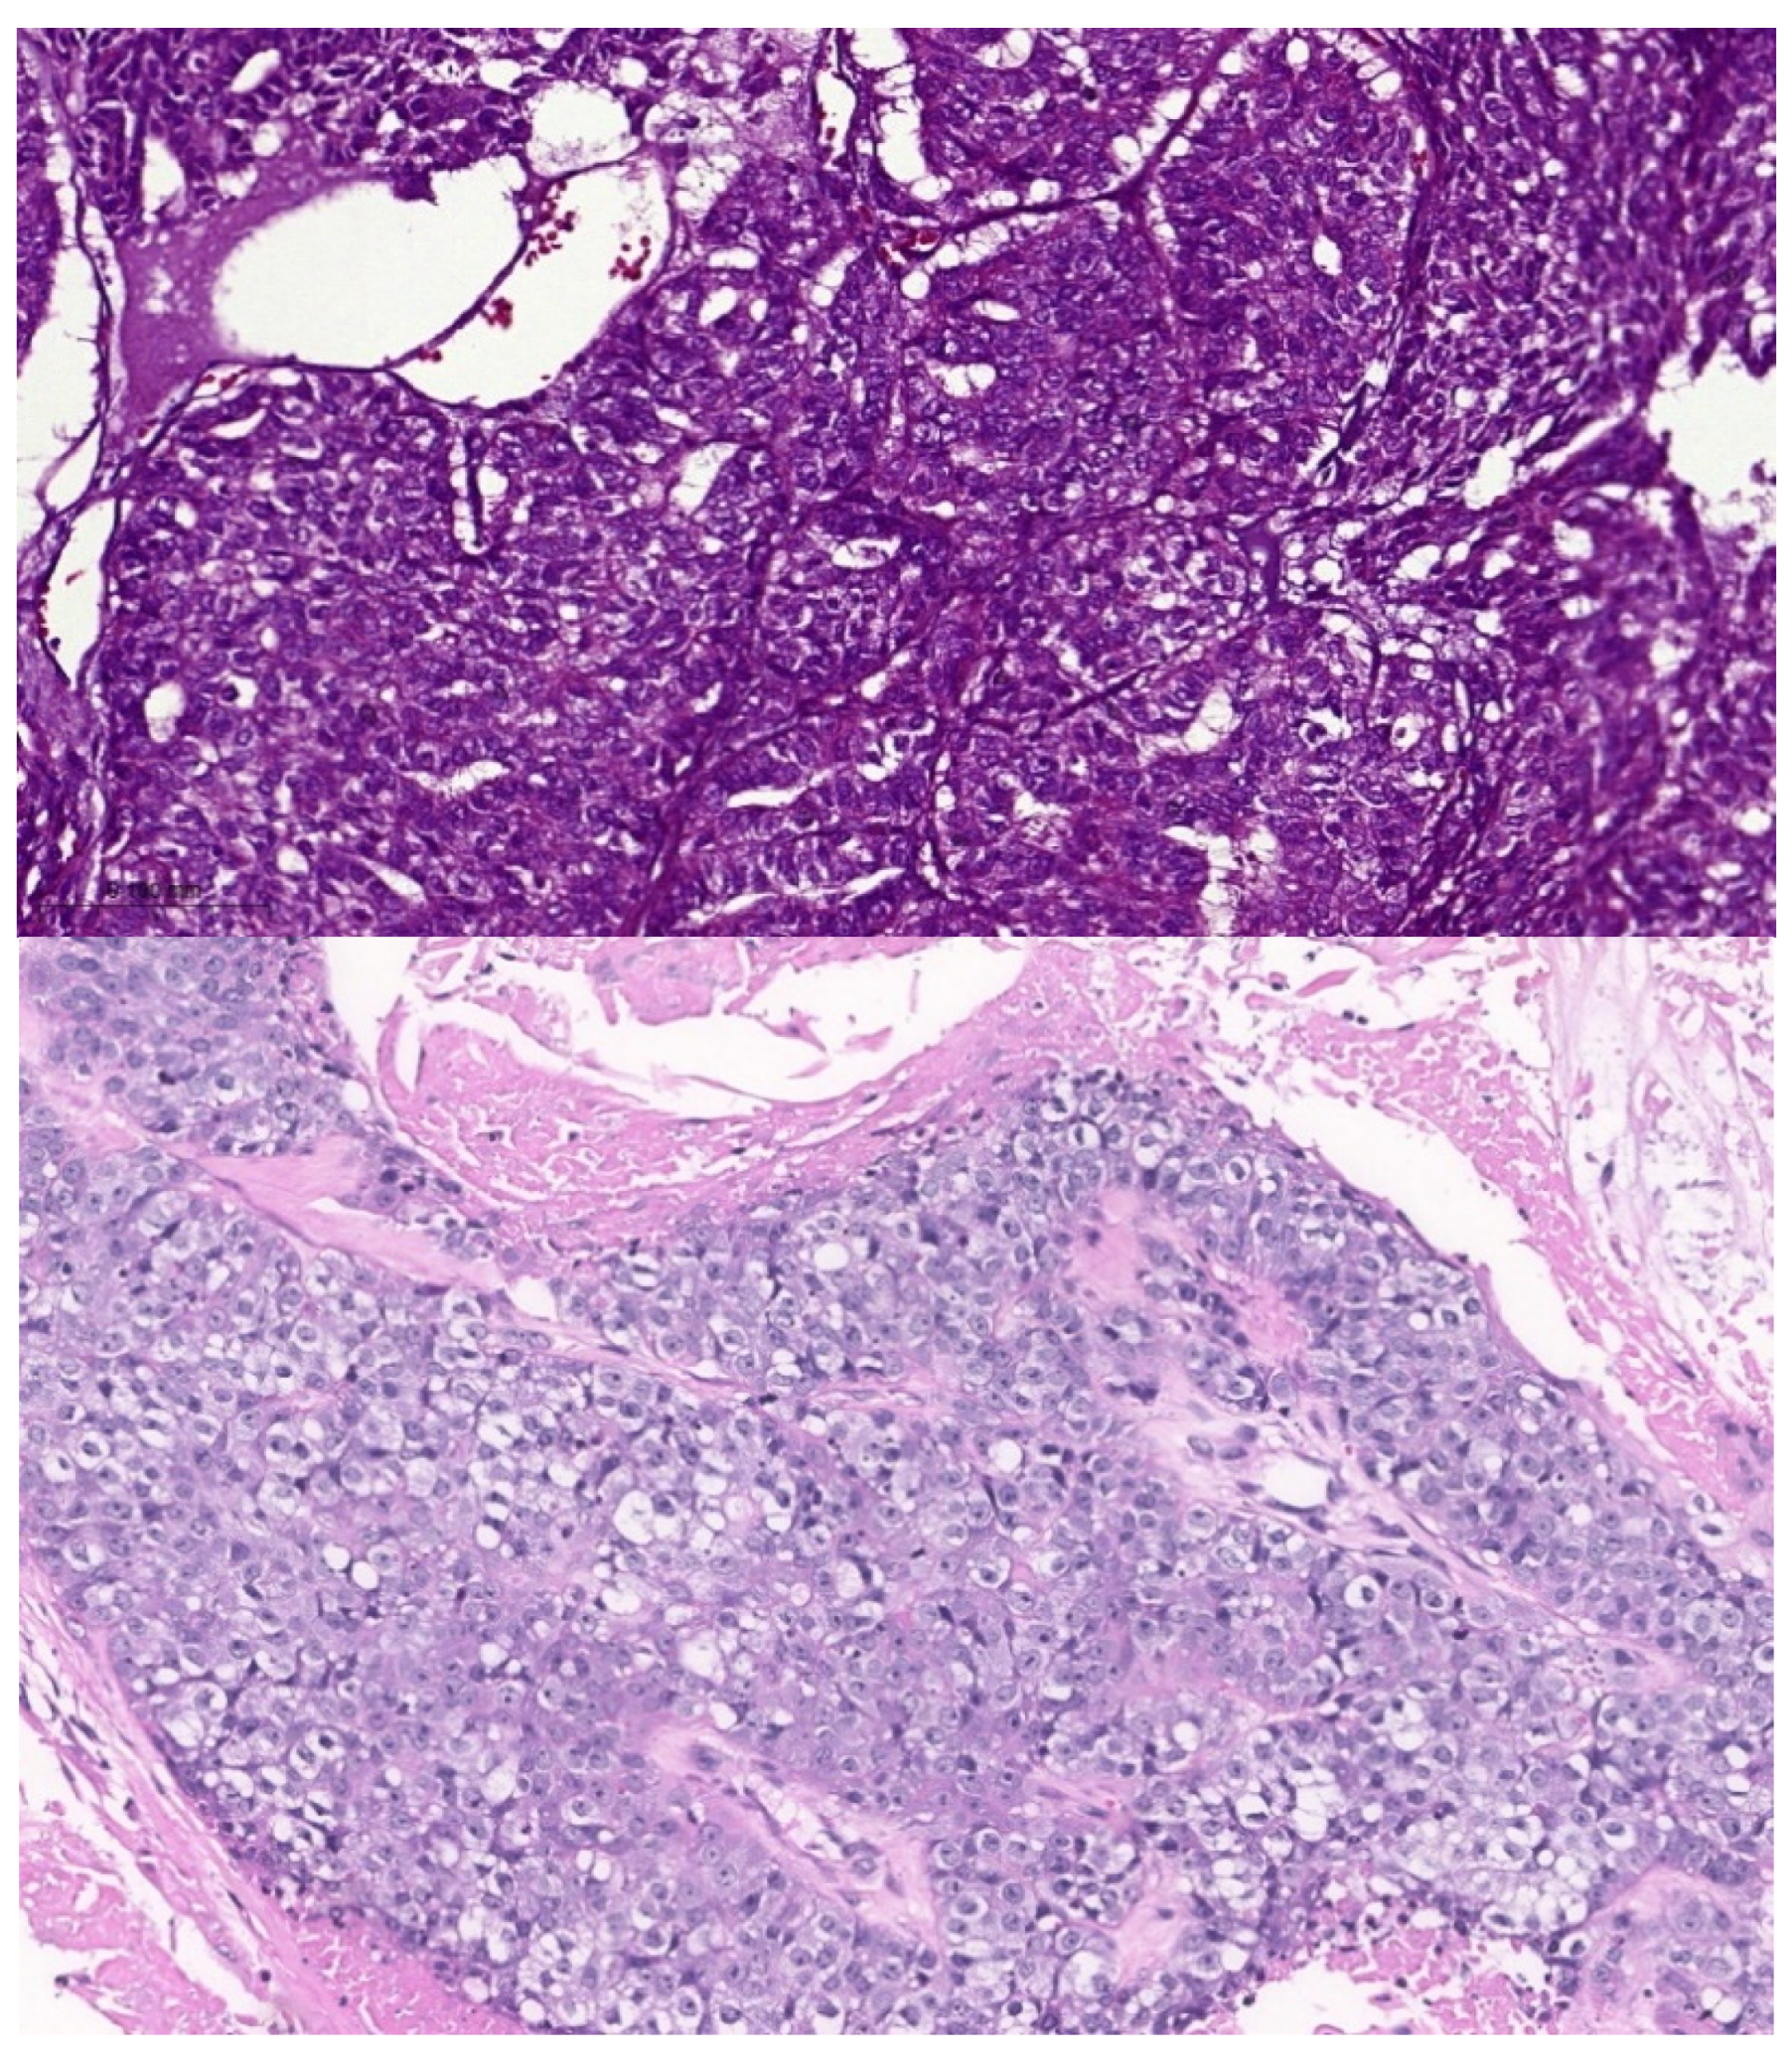

Most of the reported ASCs contained dense squamous congregations intermingled with true duct structures that showed cellular atypia. The stromal adenocarcinomatous component must be neither too superficial and inconspicuous (so as not to be considered an adenoid squamous cell carcinoma) nor very deep (so as not to be considered invasive SCC) (Figure 2). These cases are always considered high-grade. MACs are considered ASCs without an overlying SCC. For example, adnocarcinomatous lesions that secrete mucin and do not align with a particular recognized morphology (e.g., HG-MEC or high-grade mucinous cystadenomacinoma) are considered MACs. The indicated diagnostic immunohistochemical panel is rarely investigated. Figure 4 compares a case of MACs with a high-grade MEC of the minor salivary gland. Figure 5 shows a case of low-grade MAC of the lung. On the other hand, the ASCs of breast show both low-grade and high-grade features (Figure 6).

Based on the molecular heterogeneity among the studied tumors, it is difficult to consider ASCs, MACs, or high-grade MEC a subvariant of another tumor. There are sensitive markers for each lesion. Additionally, ASCs and high-grade MECs share more genetic mutations than do MACs and high-grade MECs. However, there is no specific marker that can distinguish each. Moreover, ASCs demonstrate a diverse genetic profile according to the involved site (e.g., breast, lung, pancreas, salivary glands, or gallbladder). The tendency to consider ASCs and high-grade MEC synonymous based on the clinical behavior of both is insufficient. Low-grade and high-grade ASCs were previously diagnosed (Figure 4). Panaccione et al. [67] detected a molecular involvement of FAT1, KDM6A, and KMT2D in studying metastasizing MAC. Kikuchi et al. [68] reported a case of intestinal-type adenocarcinoma of the buccal mucosa, which showed mucinous growth and negative immunoreactivity for CDX2. Our mining revealed that AKT1, ARRB1, BCL2, CDX2, MUC1, MUC16, MUC2, MUC5AC, MUC6, and CHST4 are actively involved in the oncogenesis of MACs.

Figure 5. (a,b) Low-grade ASC of breast; (c,d) high-grade ASC of breast (for illustrative purposes).